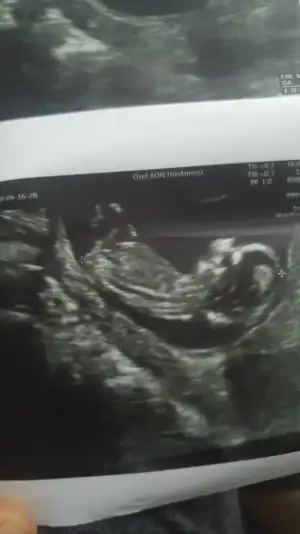

8 hafta ya göre erkek ama siz 11 12 13 hafta nub için paylaşınbize de tahmin yaparmısınız. ikisi de karından usg. ilk resim 9+4 ikincisi 8

Buna göre kızKarindan usg 7+4kizlar yorum yapacak olan varsa cok mutlu olurum